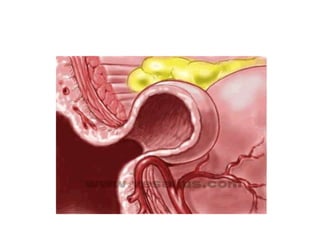

Pathogenesis of colonic diverticular

bleed

• At sites of weaknesses in the colonic wall –

where vasa recta penetrates

• Mucosa herniates thru  pseudodiverticulum

• Vasa recta draped over the dome of the

diverticulum  susceptible to trauma and

disruption

• Intimal damages  eccentric thickening 

wall weakening  rupture

Pathogenesis of colonicdiverticular bleed • At sites of weaknesses in the colonic wall – where vasa recta penetrates • Mucosa herniates thru  pseudodiverticulum • Vasa recta draped over the dome of the diverticulum  susceptible to trauma and disruption • Intimal damages  eccentric thickening  wall weakening  rupture